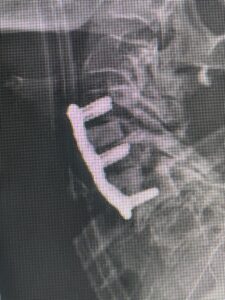

(Fig. 3) lateral intraoperative cervical x-ray demonstrating good alignment after C4-C6 anterior cervical discectomy and interbody fusion with plate. Note the interbody grafts help load-share the plate in this patient with severe osteoporosis

This 59 year-old female had severe bilateral leg pain and numbness over a 6-month period. The patient had failed conservative treatment with physical therapy, chiropractic care, and medications. MRI revealed that she had severe lumbar stenosis with a grade 1 spondylolisthesis or “slipped disc” at L5-S1 (Fig. 2). In addition, she had previously undergone both front and back surgery for severe cervical stenosis where her posterior hardware had failed because of her severe osteoporosis requiring us to remove the posterior hardware. This required her to have an anterior or front operation which allowed better fixation to her spine because of the load-sharing nature of the interbody grafts in addition to her anterior cervical plate (Fig. 3).